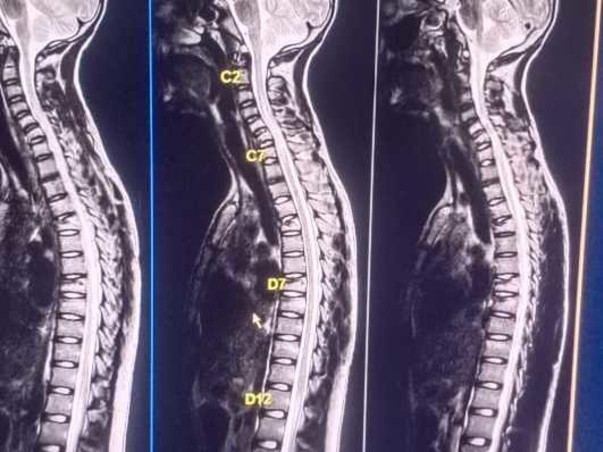

Last week, my friend dogga ramasatyam met with an accident. Due to fast spreading covid 19,their parents could not take him to the nearby hospital immediately. He struggled with his back bone pains. Then his parents decided to take him to the city hospital. In the hospital, the tests had shown that he had 5 cracks in his back bone which are shown as yellow identities in the X RAY. In this pandemic covid situation hospitals are bid to charge more. The fees is 2lakhs for his treatment. So i request you to please help my friend dogga ramasatyam from his backbone injury